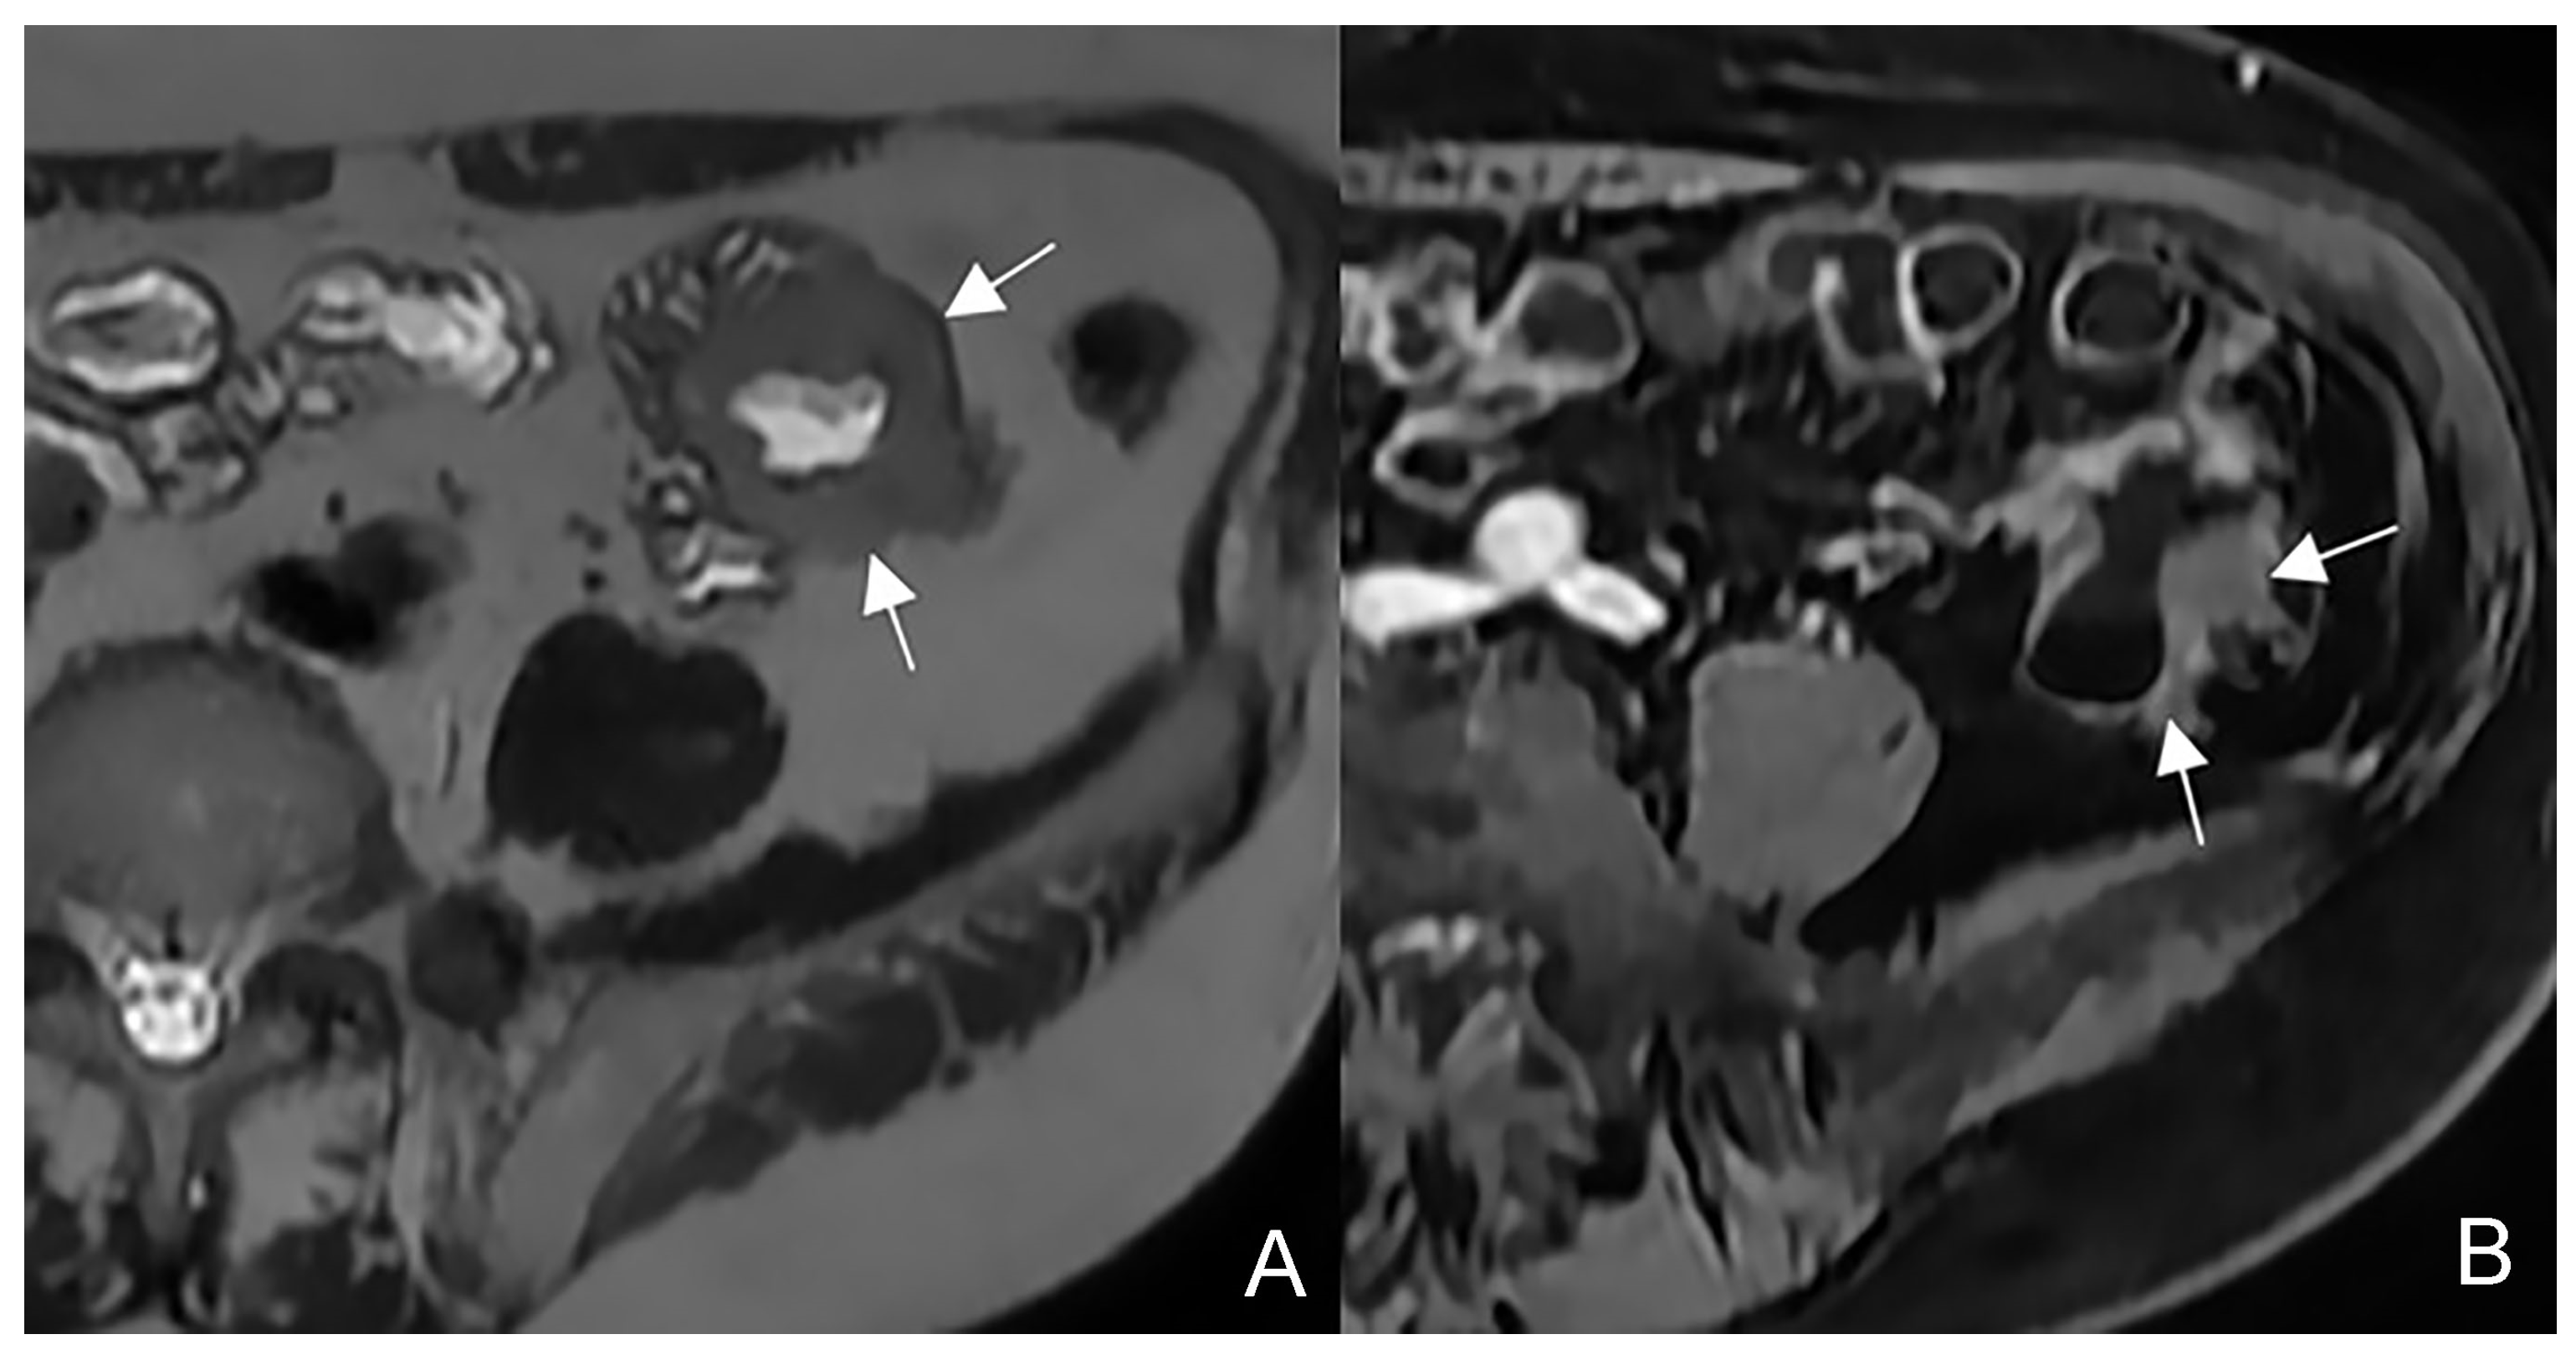

NET may present on MRI as a tiny submucosal nodule or as focal asymmetric wall thickening, with marked enhancement in the arterial phase, sometimes with hyper-vascular mesenteric enlarged lymph nodes (Figure 20). Sometimes a focal bowel wall thickening without evidence of a nodular lesion can be appreciated for the desmoplastic reaction, typical of this type of cancer. Sometimes evidence of metastases without detection of the primary tumor may occur [34,35,36,37,38,39].

Figure 20.

Example of NET in a 56-year-old female patient with abdominal pain and weight loss. (A) Axial T2-weighted, (B) DWI, and (C,D) T1-weighted after gadolinium injection images show focal asymmetric wall thickening of the distal ileum (arrow), with restriction in DWI (arrow in (B)) and marked enhancement in the arterial phase (arrow in (C,D)); an hypervascular mesenteric enlarged lymph node is also evident (arrowhead in (D)).

Other malignant disorders of the small bowel should be considered in the differential diagnosis. NET diagnosis is made when avid enhancement after gadolinium injection, desmoplastic reaction, and hyper-vascular enlarged lymph nodes are observed. NETs can become complicated with obstruction due to the desmoplastic reaction or involvement of serosa [39].